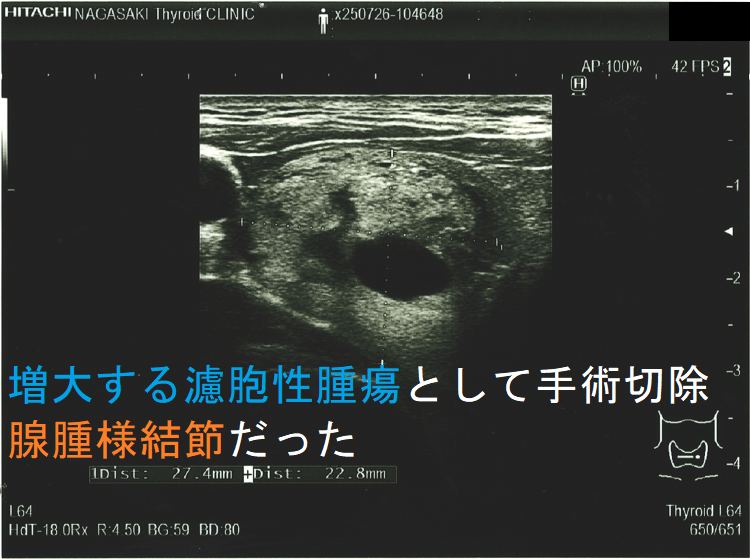

超音波(エコー)画像上、腺腫様結節と甲状腺濾胞性腫瘍は類似しますが

- 被膜があれば甲状腺濾胞性腫瘍ですが、被膜がなければ腺腫様結節[ただし腺腫様結節でも、腫瘍の境界部のハロー(halo:低エコー帯)は、不完全な形で存在します]

- ハローが全周性に認められれば、甲状腺濾胞性腫瘍の可能性が高い。(ただし、ハローの一部途絶、 肥厚等は甲状腺濾胞癌の可能性を考えます。)

- 中心に達する栄養血管がなければ腺腫様結節ですが、あれば甲状腺濾胞性腫瘍・腺腫様結節いずれの可能性もあります。

- 腺腫様甲状腺腫:14 例(10%);やはり、エコー・細胞診での鑑別が難しいものがありますので